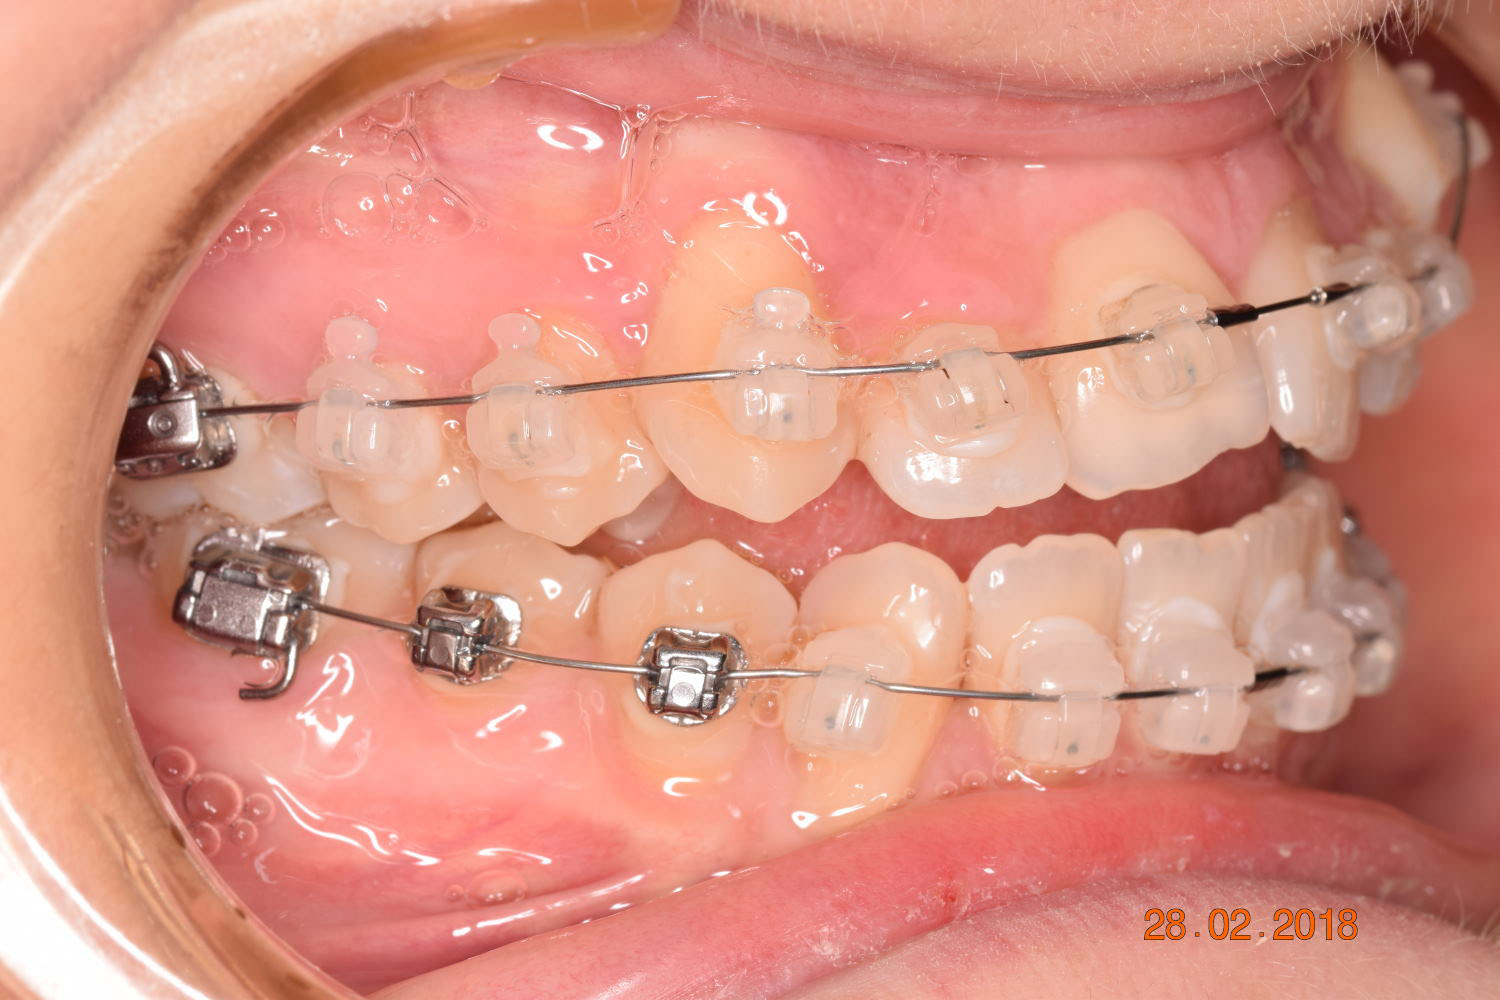

The results were unsatisfactory and the patient began losing interest in the treatment. Dr. Coca and the patient agreed to extend the treatment for six more months and then stop, regardless of the outcome.

The teeth are in a very good position and the bone has reshaped.

This case posed challenges in all three spatial dimensions, compounded by significant crowding. The patient was highly compliant and maintained excellent oral hygiene throughout the 5.5 years of treatment, which required more than 30 clinical appointments.

The facial changes are impressive considering treatment involved only conventional orthodontics and not orthopedic interventions, TADs, or surgery.